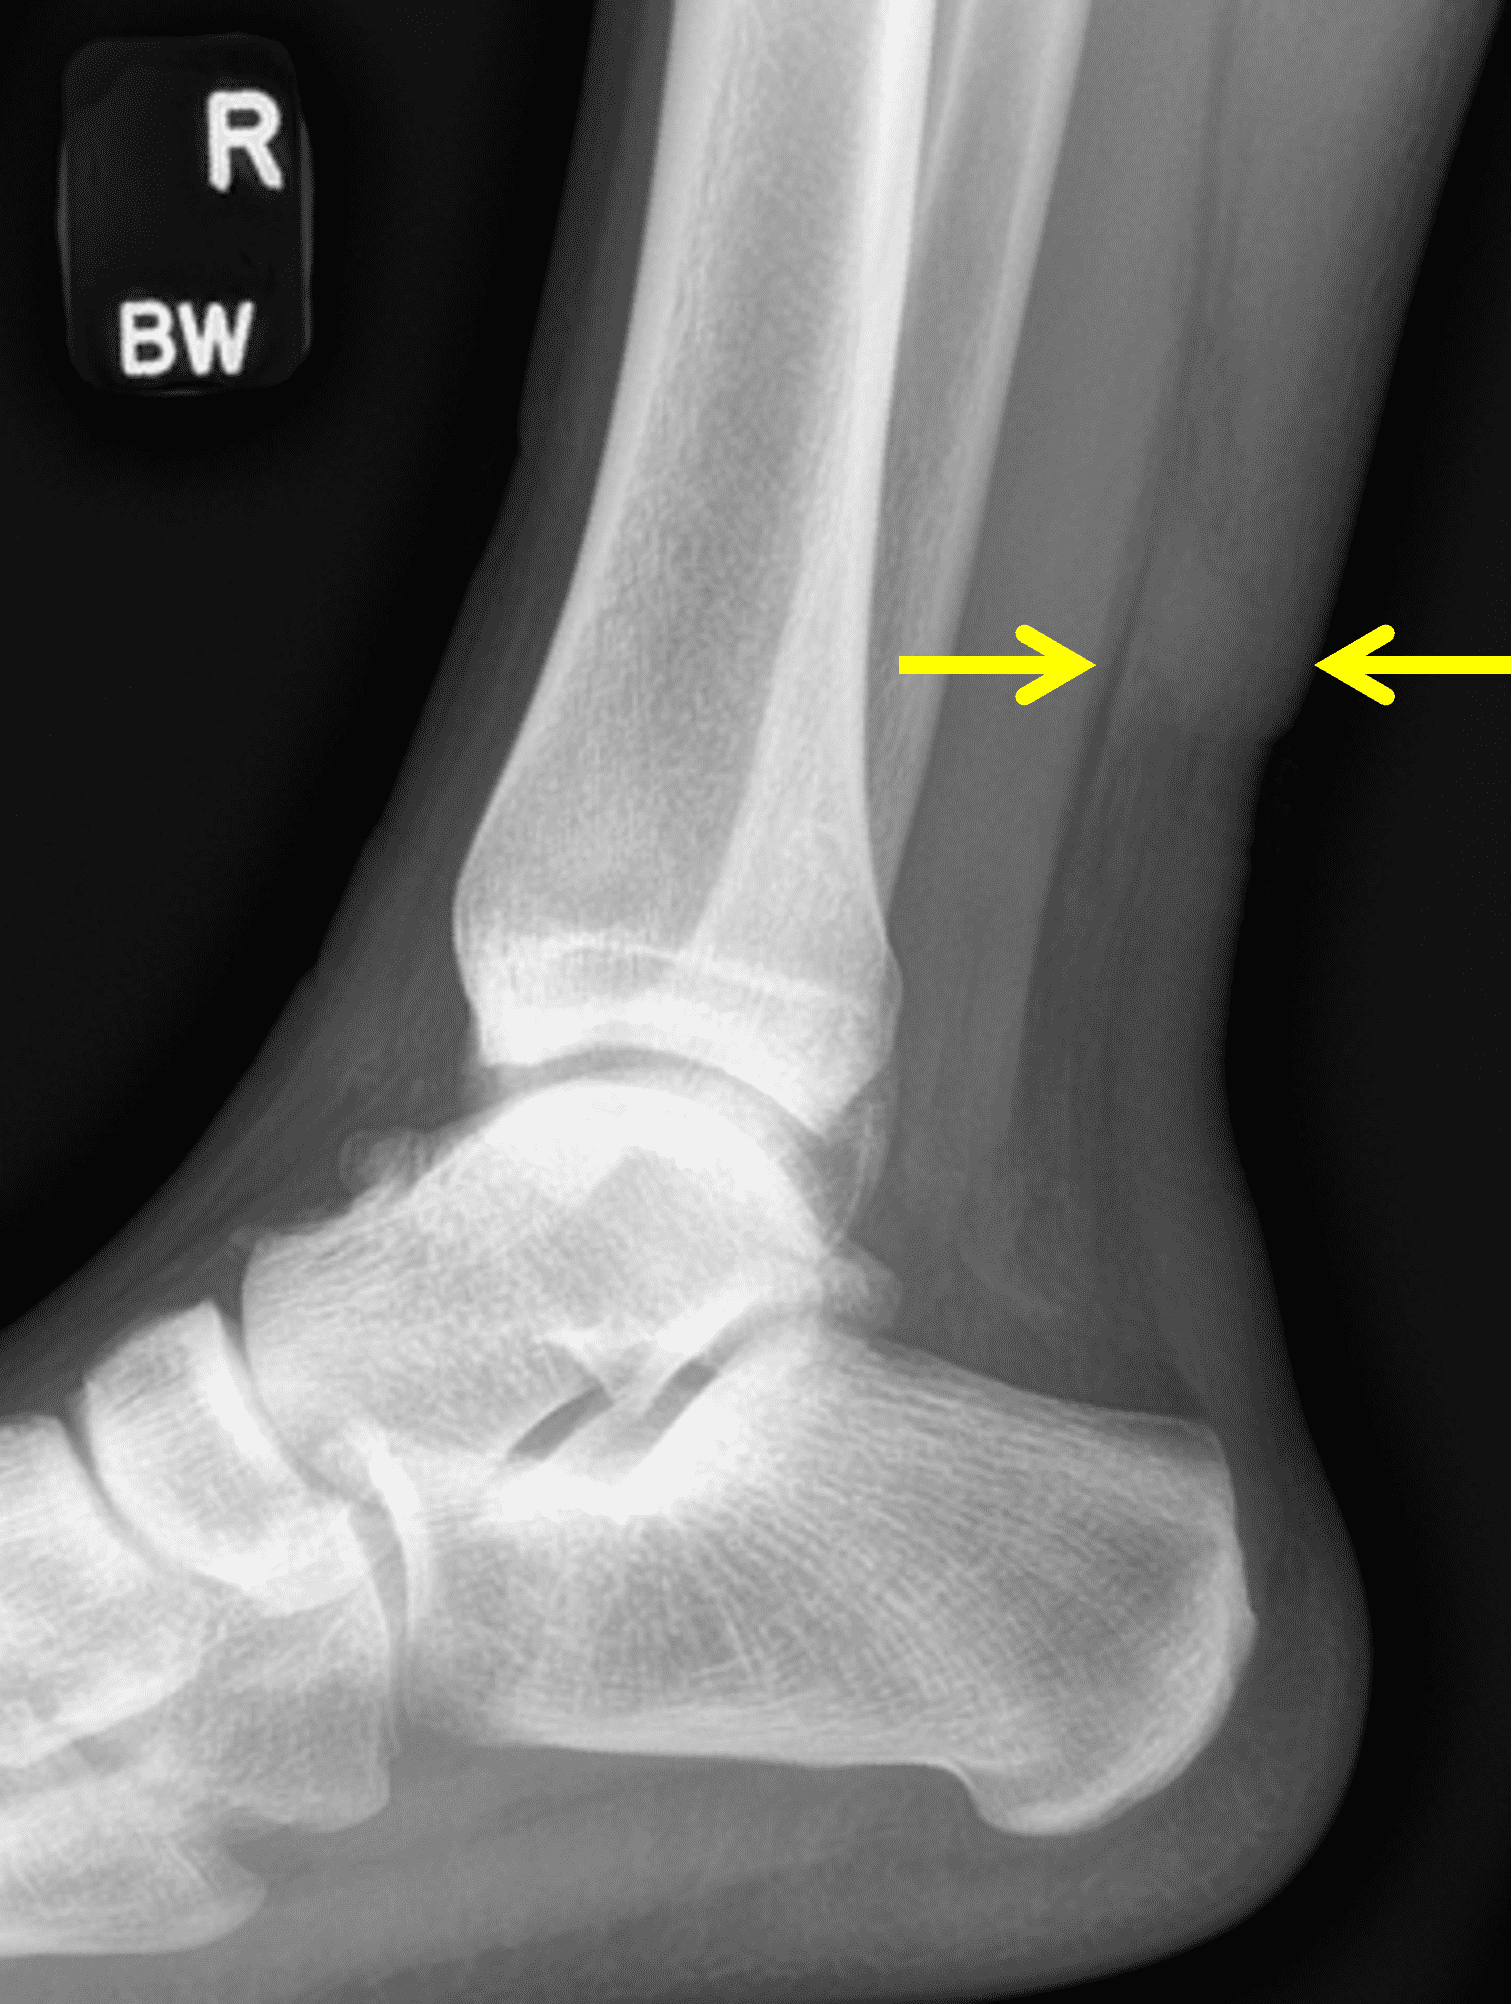

A 22 year-old male college football player presents with a “pop” and pain posterior to the right ankle during practice 1 week prior. He is unable to bear weight. Lateral radiograph (1A), sagittal fat-suppressed T2-weighted (1B), sagittal T1-weighted (1C), and transverse fat-suppressed T2-weighted images are provided. What is your diagnosis? What MRI findings affect clinical management decisions?

Figure 2: Complete Achilles tendon rupture. (2A) The lateral radiograph shows a thick and indistinct proximal Achilles tendon contour (arrows). (2B) A fat-suppressed T2-weighted image shows complete rupture of the tendon with a fluid-filled gap (yellow arrow) measuring 1.5 cm in length, located 10 cm cranial to the tendon insertion (blue arrow) and just distal to the edematous myotendinous junction (red arrow). The tear is superimposed on diffuse tendinosis. (2C) A sagittal T1-weighted image confirms the diffuse tendinosis. Fluid extends anteriorly into Kager’s fat pad (arrow) suggesting disruption of the anterior paratenon. (2D) A transverse fat-suppressed T2-weighted image through the proximal tendon shows no intact fibers (arrow), confirming the full-thickness rupture.